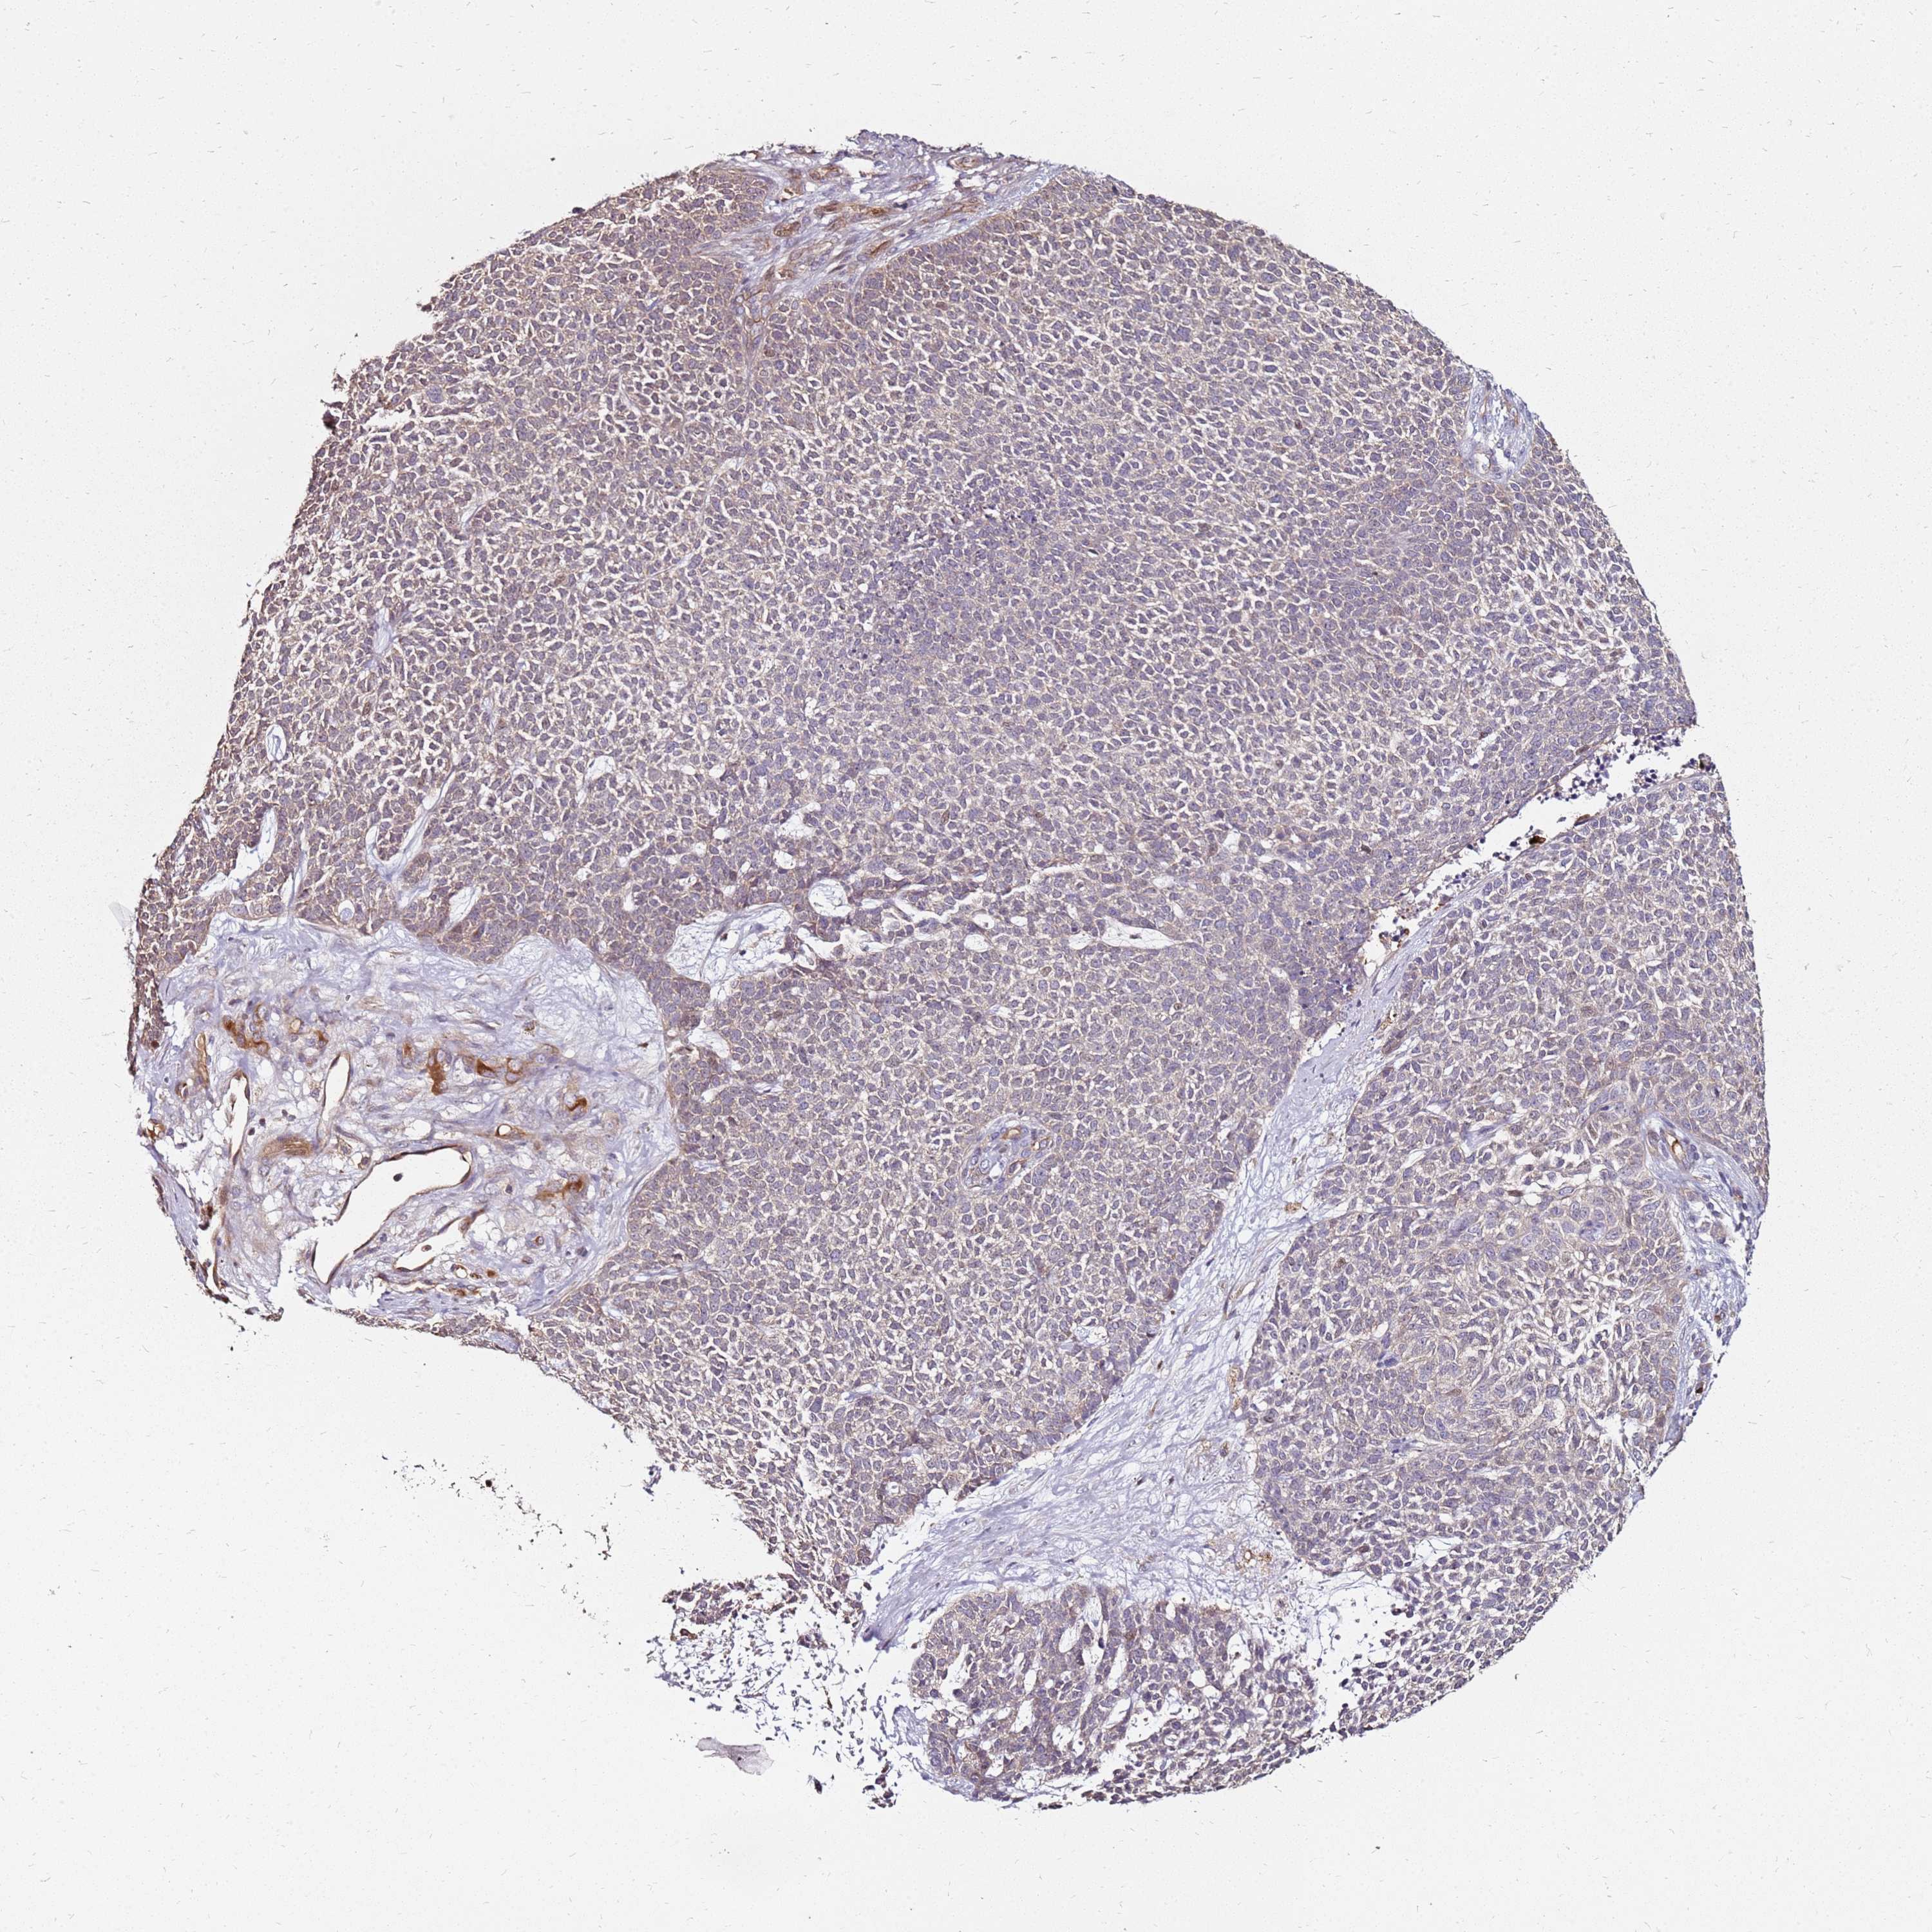

CANCER SKIN CANCER Show tissue menu

Basal cell and squamous cell cancer

SKIN CANCER - Protein expressioni

A mouse-over function shows sample information and annotation data. Click on an image to view it in a full screen mode. Samples can be filtered based on level of antibody staining by selecting one or several of the following categories: high, medium, low and not detected. The assay and annotation is described here.

Antibody stainingi

Antibody staining in the annotated cell types in the current human tissue is reported as not detected, low, medium, or high, based on conventional immunohistochemistry profiling in selected tissues. This score is based on the combination of the staining intensity and fraction of stained cells.

Each image is clickable and will lead to virtual microscopy that enables deeper exploration of all samples and also displays staining intensity scores, fraction scores and subcellular localization as well as patient and tissue information for each sample.

Antibody HPA045781

Staining

High

Medium

Low

Not detected

Intensity

Strong

Moderate

Weak

Negative

Quantity

>75%

75%-25%

<25%

None

Location

Nuclear

Cytoplasmic/membranous

Cytoplasmic/membranous,nuclear

Basal cell carcinoma

Squamous cell carcinoma, NOS

Squamous cell carcinoma, metastatic, NOS